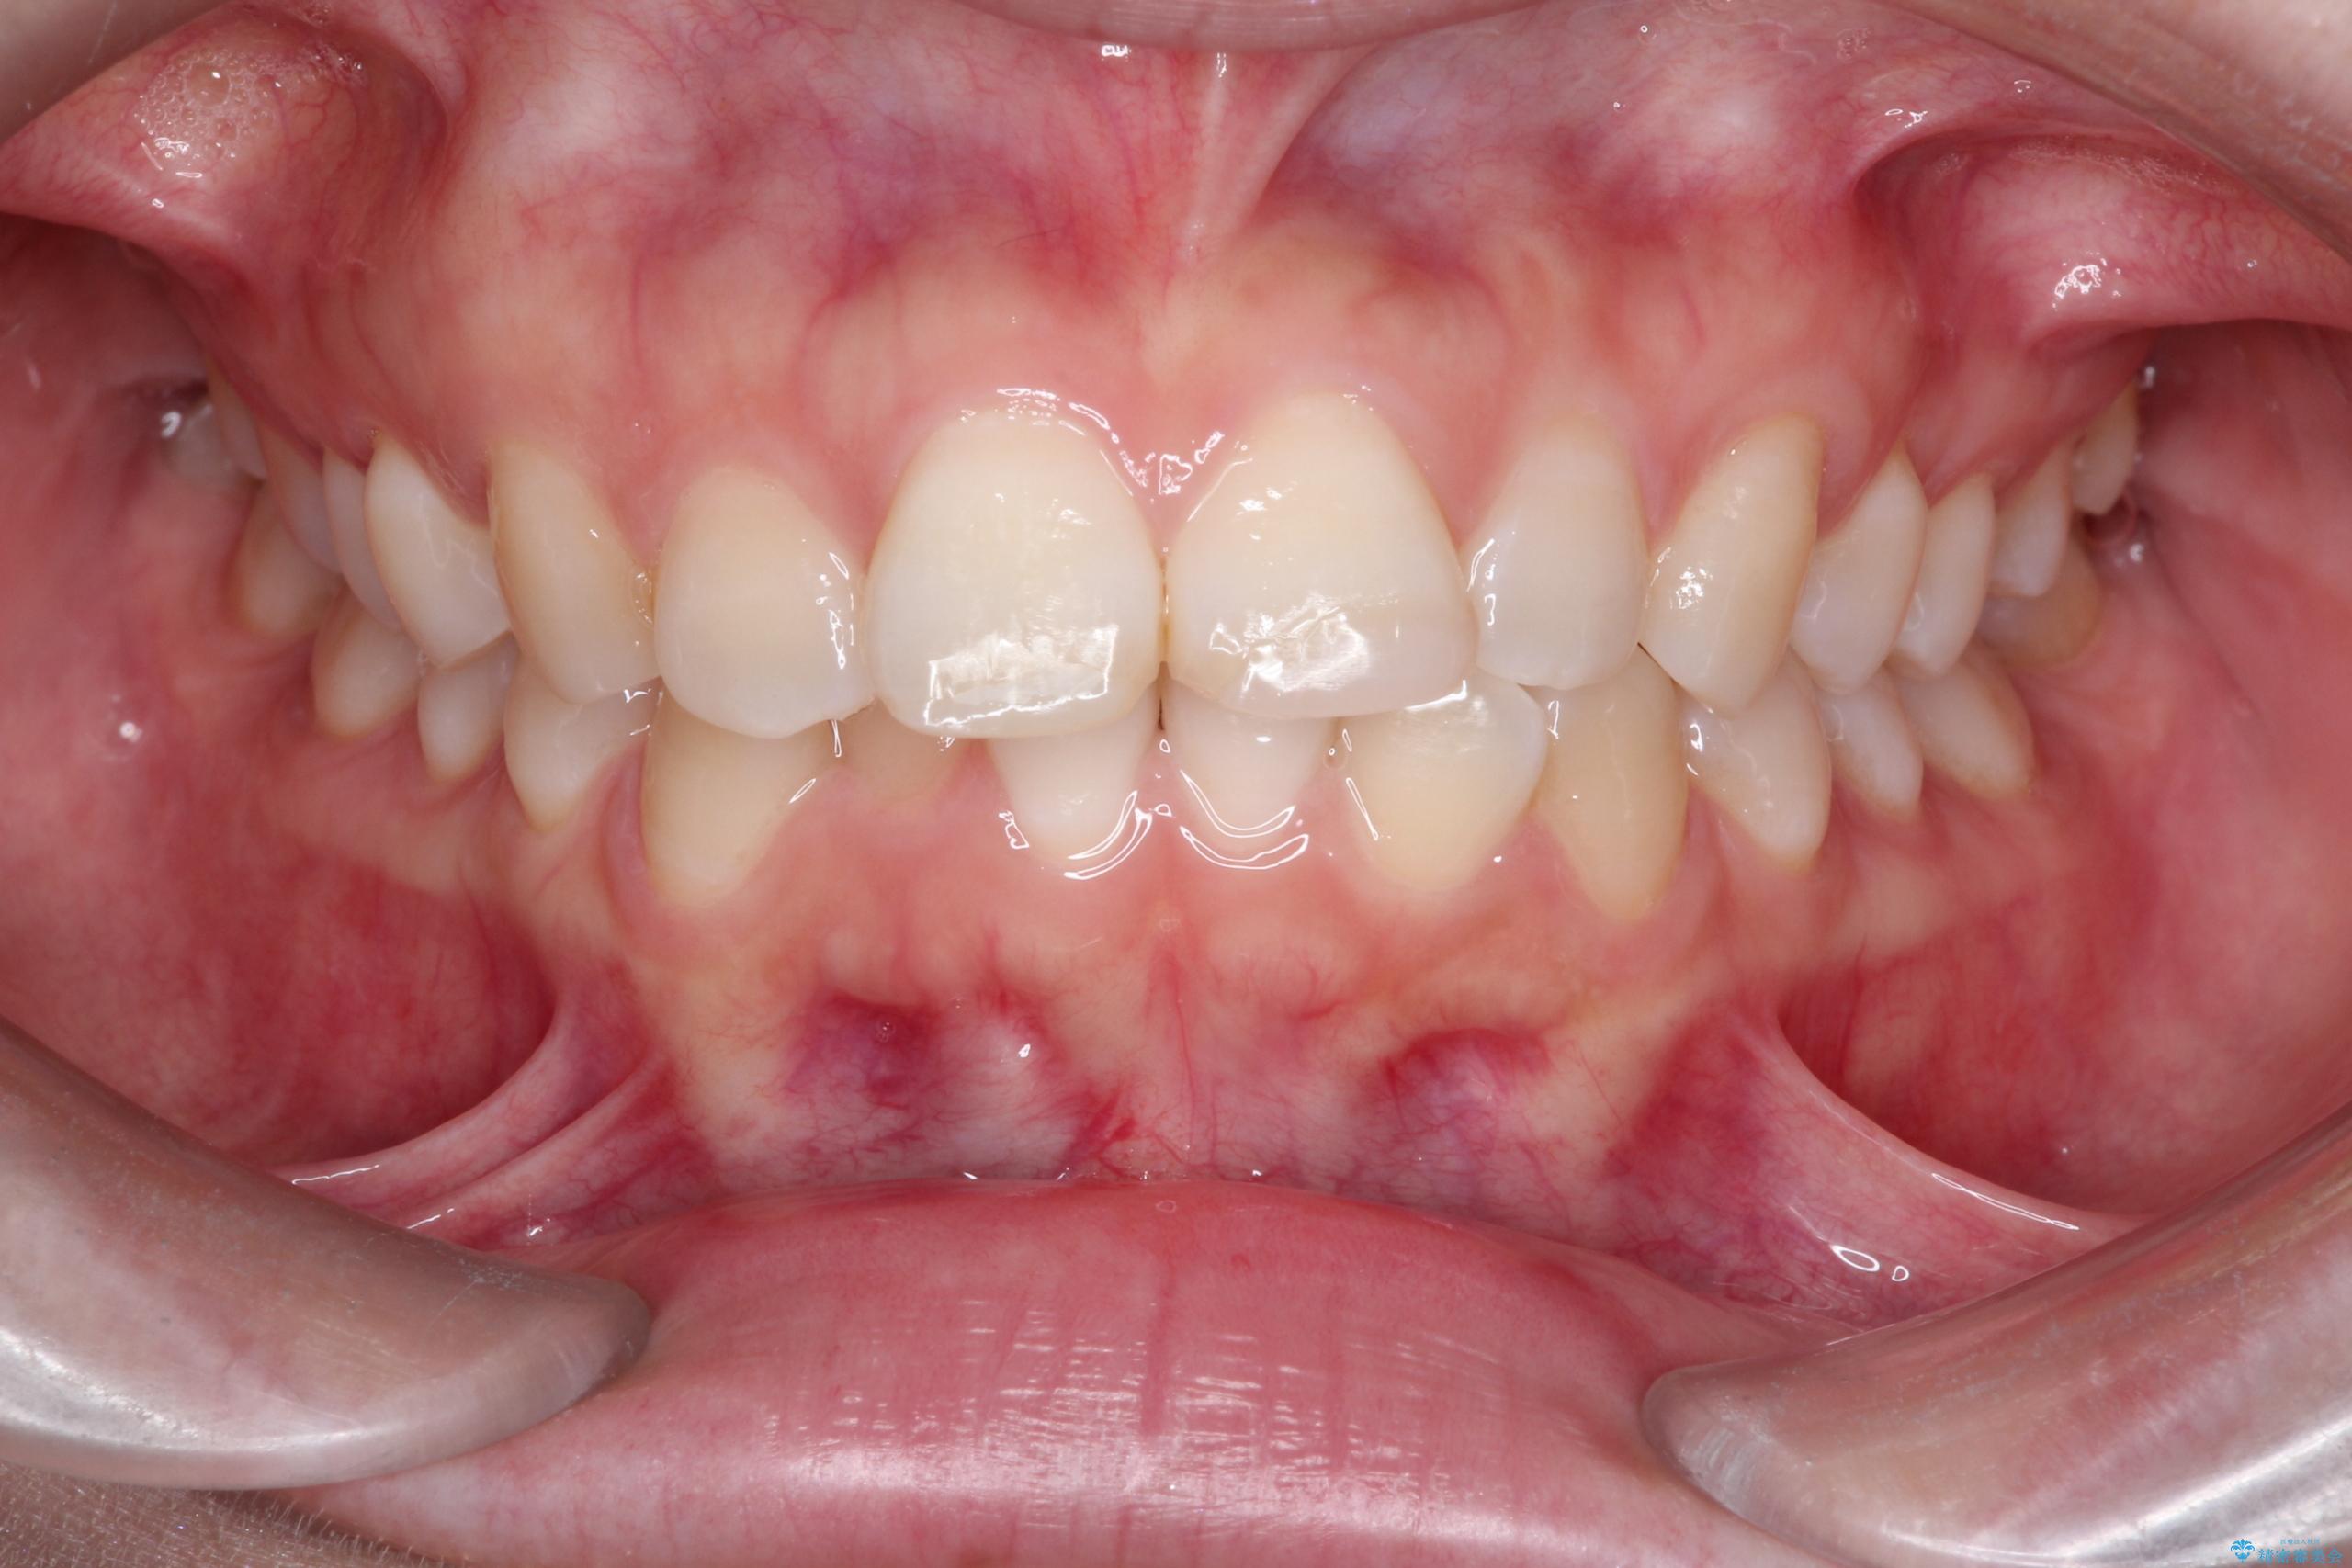

- 前歯のデコボコ(叢生)を気にされてご来院されました。精密な検査の結果、歯が並ぶスペースが不足していることが判明。患者様のご希望から、透明で目立ちにくいインビザライン(マウスピース矯正)による治療計画を立案しました。抜歯を避け、奥歯全体を奥へ動かす遠心移動という方法でスペースを確保し、前歯の叢生を解消することを目指します。

今回の矯正治療では、透明なマウスピース型の装置インビザラインを使用しました。この装置は取り外し可能で、日常生活で目立ちません。治療は、緻密に計算された計画に基づき、段階的に作製されたマウスピースを交換していくことで、奥歯から順に全体を後方へ移動させる遠心移動を実施。これにより、前歯を並べるための十分なスペースが確保され、デコボコが解消されました。抜歯することなく、機能的にも審美的にも整った美しい歯並びを獲得していただけました。